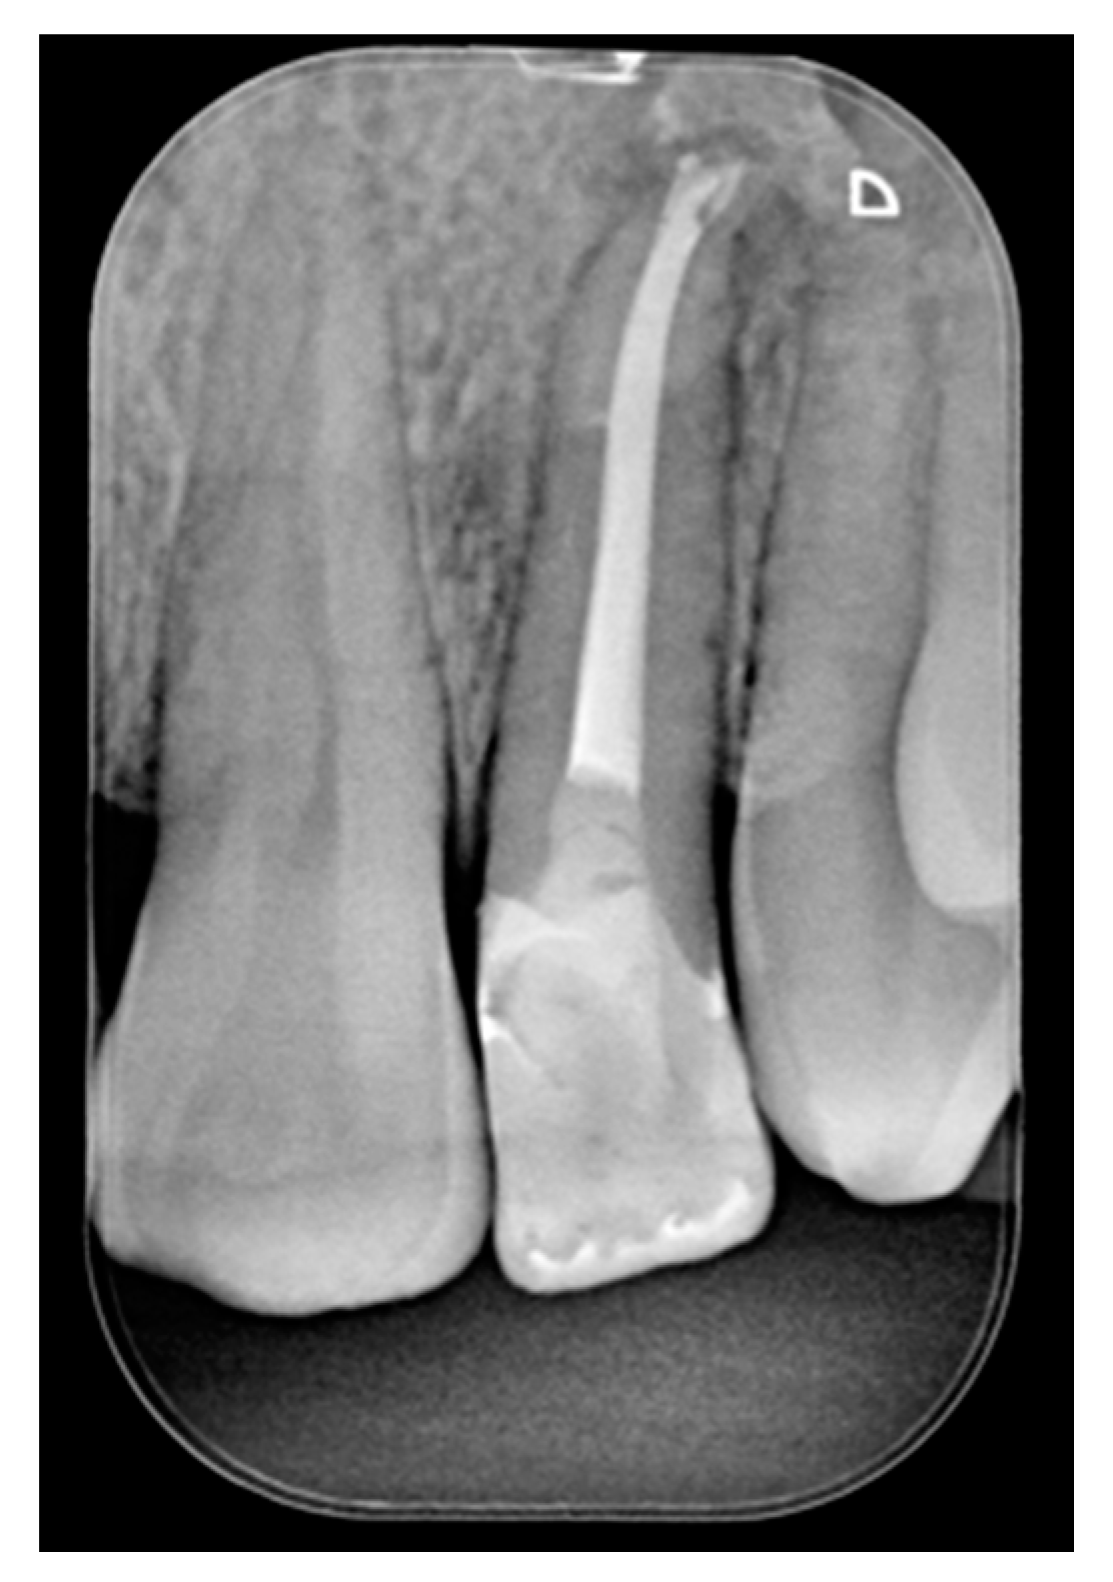

A 42-year old woman presented to the clinic with esthetic concerns related to her upper left lateral incisor (Figure 20). Pre-operative x-rays showed periapical lesion that required retreatment. After retreatment (Figure 21) a treatment plan was proposed to the patient. The ideal treatment would have involved an orthodontic therapy to gain back lost space in mesial portion. The patient decided not to consider an orthodontic treatment and accepted just the restorative proposal (Class IV restoration). Considered the sufficient amount of ferrule no post was applied [16]. Shade was selected as described in previous case, using the button-try technique [14]. After isolation with rubber dam, preparation (Figure 22) and adhesion (Clearfil SE, Kuraray Noritake Dental, Tokyo, Japan), composite frame was completed (Clearfil Majesty ES-2, A1D, Kuraray Noritake Dental, Tokyo, Japan) with silicone index and interproximal transparent mylar matrices (Figure 23). Interproximal walls were considered too thick; therefore, they were reduced (Figure 24) using diamond bur as described in Section 2.1.2. This allowed the internal dentinal body to have the correct volume (Figure 25) and therefore to respect ideal opacity/translucency ratios. Restoration was therefore completed adding enamel layer (Clearfil Majesty ES-2, A1E, Kuraray Noritake Dental, Tokyo, Japan) and performing finishing and polishing procedures (Figure 26 and Figure 27) as described in previous clinical case. The restoration shows good integration 6 months post-operative (Figure 28 and Figure 29).

Figure 20.

Initial clinical situation. Reprinted from Restauri diretti nei settori anteriori, G. Paolone, S. Scolavino, © 2021, with permission from Quintessence Publishing Italy.

Figure 21.

Initial x-ray, during and after endodontic retreatment. Reprinted from Restauri diretti nei settori anteriori, G. Paolone, S. Scolavino, © 2021, with permission from Quintessence Publishing Italy.